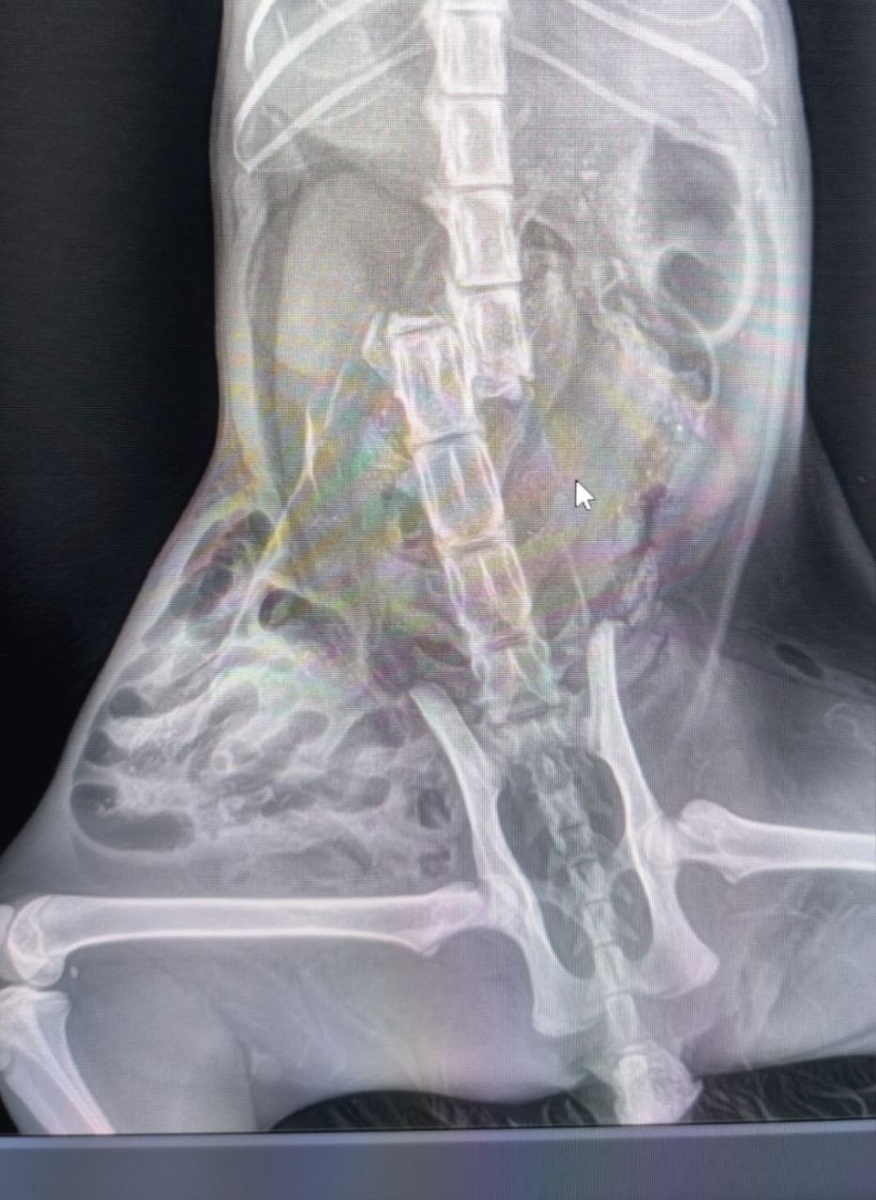

Я чувствовала тошноту. А она… она просто сидела и смотрела на меня. Ее зовут Черничка. Несколько дней назад мне позвонили с заправки и сказали, что к ним кошку подкинули. Я попросила напомнить мне, чтобы я приехала забрать. Но жизнь, в лице проезжающей машины, добралась до нее первой. Переехала. Мне так жалко эту кошечку, что до сих пор нахожусь в некотором ступоре и не могу вернуться в норму. Но она выжила, вопреки всем прогнозам врачей. Сколько всего они сделали: и тут подлатали, и там прокапали, и здесь зашили. Черничка оказалось не тихой страдалицей, а активной и бойкой девочкой, которая теперь постоянно «куда-то бежит». Только бежит она на двух передних лапах, а половина ее тела безвольно волочится сзади - и тут никакой чудо-врач не изменит того, что она больше никогда не будет ходить. Ей не больно, она не замечает ничего необычного в себе и ощущает себя вполне самодостаточной кошкой. Людей еще побаивается и не представляет, что теперь она навсегда зависит от человеческой помощи

Но она выжила, вопреки всем прогнозам врачей. Сколько всего они сделали: и тут подлатали, и там прокапали, и здесь зашили. Черничка оказалось не тихой страдалицей, а активной и бойкой девочкой, которая теперь постоянно «куда-то бежит». Только бежит она на двух передних лапах, а половина ее тела безвольно волочится сзади - и тут никакой чудо-врач не изменит того, что она больше никогда не будет ходить. Ей не больно, она не замечает ничего необычного в себе и ощущает себя вполне самодостаточной кошкой. Людей еще побаивается и не представляет, что теперь она навсегда зависит от человеческой помощи.

Прошла уже почти неделя. Можно с гордостью делиться успехами: Черничка боец, мы ее не бросили, доктора проявили весь свой талант. А до сих пор у меня внутри карусель из «за что», «а если бы ее не подкинули на заправку», «а если бы раньше позвонили», «а если бы раньше приехала», «что делать дальше». Вопросы, на которые нет явных ответов.